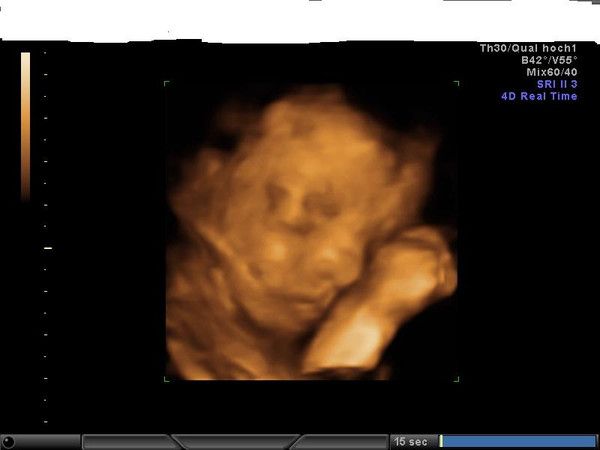

Mami werden ist toll.

Hier sehen Sie alle Fotos dieses Clubs.